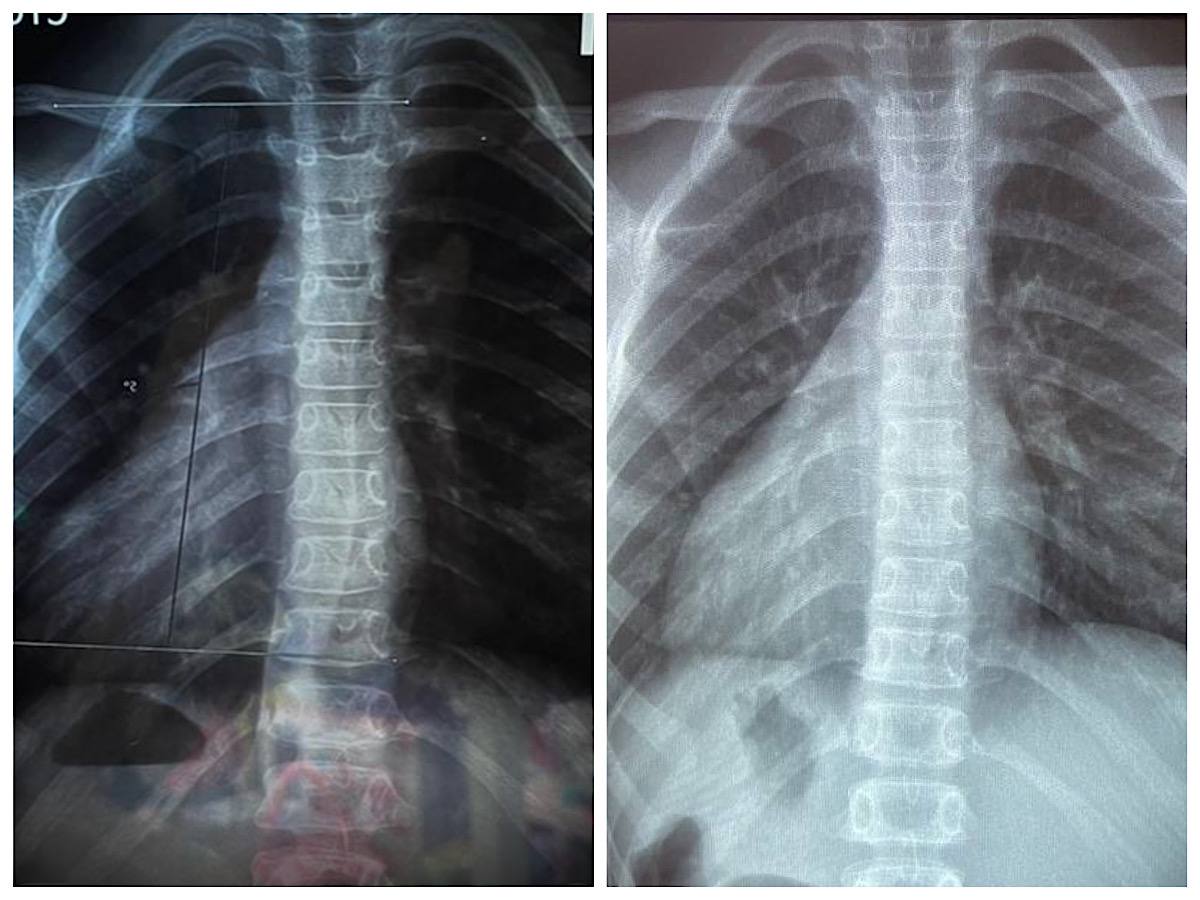

Девочка 7 лет, Риссер 0 (костный пост не завершен).

Сколиоз 11° и 7° градусов по Коббу

Ротация по сколиометрии 5° в грудном и поясничном отделах позвоночника.

Фронтальный дисбаланс 1 см.

Визуально видна разница уровней плеч, лопаток, треугольников талии.

🔸Уменьшили угол Кобба в грудном отделе с 11° до 8°

🔹Уменьшили ротацию тела с 5° до 2° в грудном отделе.

🔹Вывели во фронтальный баланс.